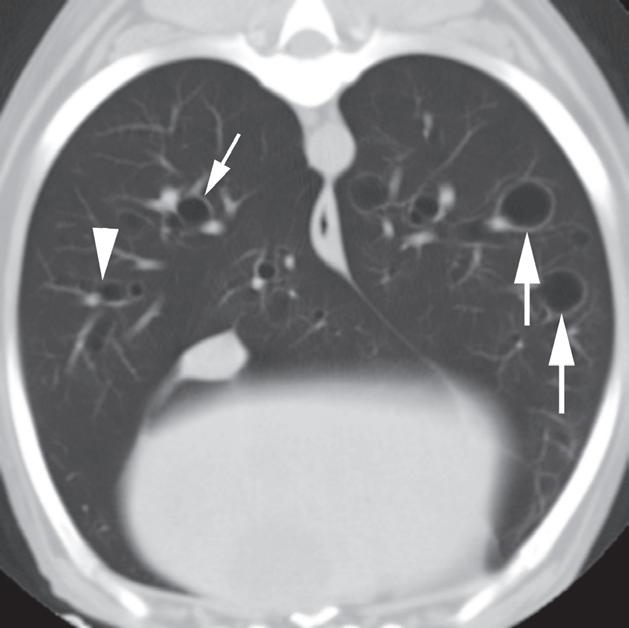

Rycina 4.6.3. Pęcherze płucne (pies) TK

Badanie wykonano u 13-letniego foksteriera z pojedynczym gruczolakorakiem płuc (nie ukazano na rycinie).

Reprezentatywne obrazy TK środkowej i doogonowej części klatki piersiowej, uporządkowane od strony doczaszkowej do doogonowej, ujawniły liczne cienkościenne pęcherze o różnej wielkości. Pęcherze były kuliste i odróżniały się od rurowatego kształtu dróg oddechowych podczas oglądania kolejnych obrazów. Miały również większą średnicę, niż można by oczekiwać w przypadku dróg oddechowych na obwodzie płuca (a–c – duże strzałki). W przeciwieństwie do pęcherzy, drogi oddechowe się rozgałęziały (c – grot strzałki) i towarzyszyły im tętnice oraz żyły płucne (b, c – małe strzałki). U tego pacjenta pęcherze nie powodowały żadnych objawów klinicznych i uznano je za rozwojowe. Ocena makroskopowa i mikroskopowa zmian z usuniętego podczas lobektomii płuca potwierdziła rozpoznanie obrazowe